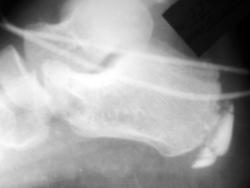

Ребенок М.11лет жалуется на боли в пятках, в конце дня, травмы не было

єто две стопы !

Похоже на Хаглунда

Тогда надо снять аксиалы.

Рентгенография обязательна, но не для подтверждения диагноза, а скорее для исключения других причин боли в пятке. Часто обнаруживаемая неровность пяточного росткового хряща не обязательно свидетельствует об остеохондропатии бугра пяточной кости. Еще не помешало бы увидеть, кроме «шероховатости» бугра пяточной кости, уплотнение и фрагментацию апофиза.